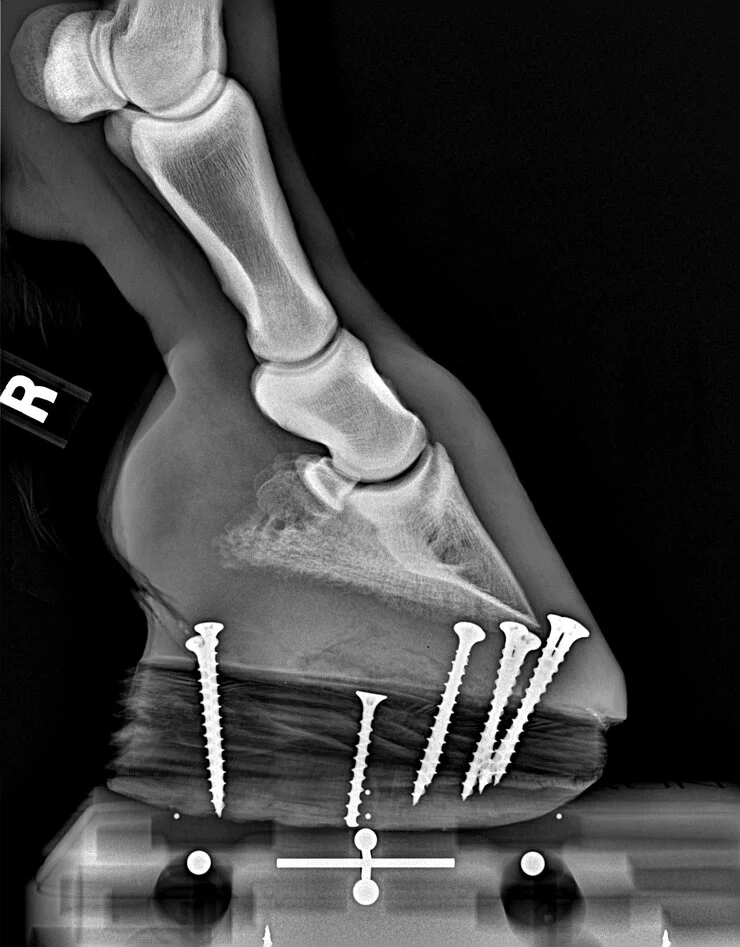

Many hoof and lameness conditions are best treated when a vet and farrier work closely together.  Orange County Equine will work closely with your farrier to ensure foot and leg health. Often times, radiographs are used to guide trimming and shoeing to optimize the outcome of conditions such as laminitis, club feet, quarter cracks, white line disease, etc. During our consults we do not charge per x-ray taken in order to ensure our vets and the farriers have all of the information they need to optimize care and not be limited.

In addition, many causes of lameness benefit from therapeutic farriery.  After the source of lameness is identified, biomechanics of the affected anatomy is considered and a shoeing plan will be developed to achieve the desired biomechanics.